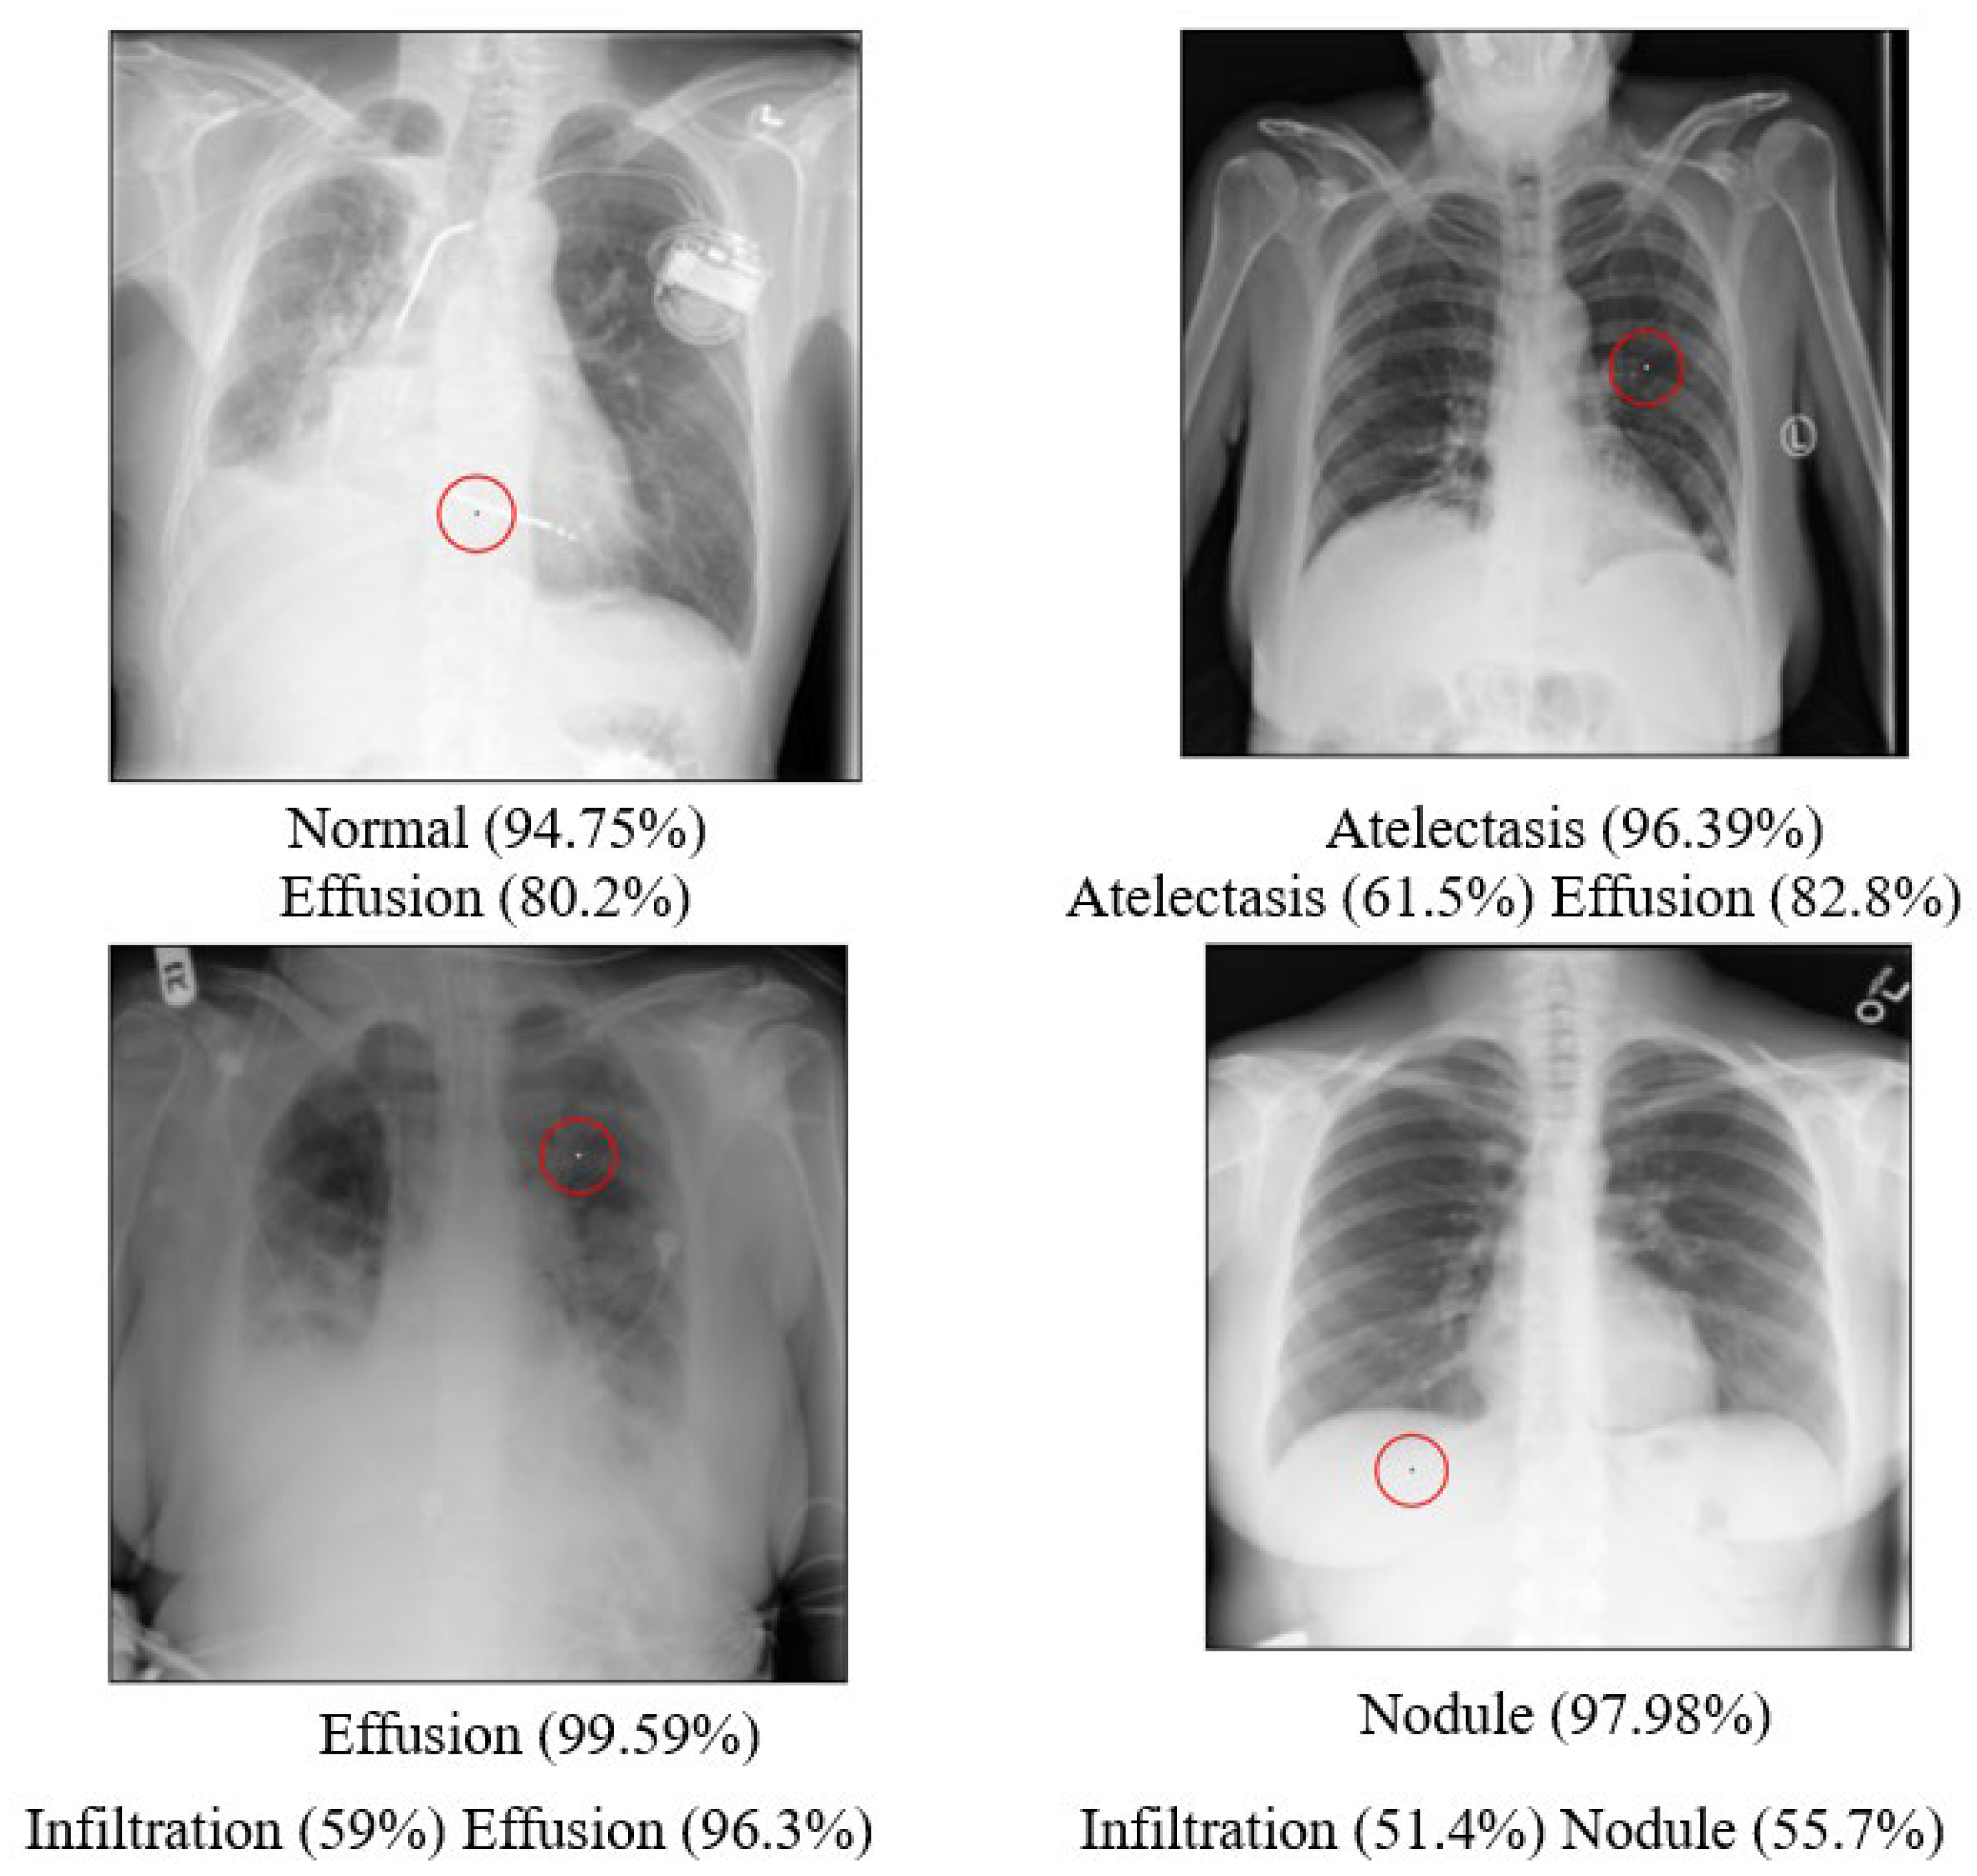

The results of the attacks for the Chest dataset, specifically five categories, are presented in Table 28. 4981 of the total 5508 images were successfully attacked, resulting in an overall attack success rate of 90.43%. When calculating the success rate of each category separately, the average success rate of attacks for the entire dataset was 89.166%. While the success rates of most categories were high, they were lower than 80% for the “Nodule” category. This may have been because a smaller number of data points were available for this category, resulting in a biased estimation.

The high success rate of attack for this dataset could be due to its nature as a binary classification multi-label dataset with 14 labels defining the image categories. Even a slight perturbation on the image could cause the confidence levels of the various labels to fluctuate. If the confidence level of a previously high-confidence label decreases, or if any of the other 13 labels surpass a certain threshold, a change in category is likely to occur. The attacked images that were successful in achieving classification transformation are illustrated in Figure 17 below.

The average denoising results for each model on the Chest dataset are shown in Table 29 below. The images of the Chest that were successfully attacked with One-Pixel attacks are, respectively, shown in Figure 18, along with the reconstructed images after being denoised by each model.